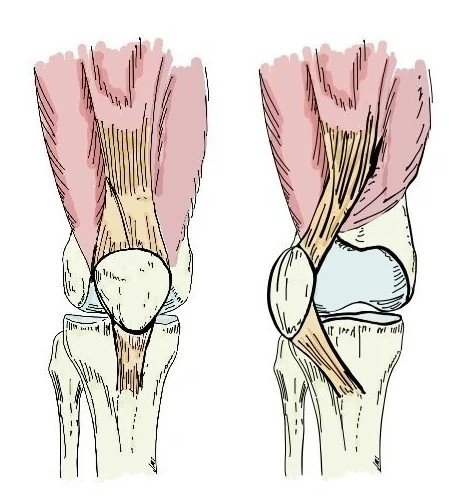

Meniscus Repair is a surgical procedure to treat tears in the meniscus, which is a C-shaped cartilage in the knee joint acting as a shock absorber between the thigh bone (femur) and shin bone (tibia). The meniscus plays a critical role in stabilizing the knee, distributing weight, and preventing early arthritis.

When the meniscus is torn due to injury or degeneration, repairing it rather than removing it (meniscectomy) is often preferred, as it helps preserve knee function and reduces the risk of long-term joint damage.

The Posterior Cruciate Ligament (PCL) is located inside the knee joint and works with the Anterior Cruciate Ligament (ACL) to stabilize the knee. While PCL injuries are less common than ACL injuries, they are often more complex and sometimes occur in combination with multi-ligament knee injuries.

The Anterior Cruciate Ligament (ACL) is one of the main stabilizing ligaments in the knee. It connects the thigh bone (femur) to the shin bone (tibia) and helps maintain knee stability, especially during twisting, pivoting, or sudden movements.

An ACL injury—often caused by sports, accidents, or sudden knee trauma—can lead to knee instability, pain, and difficulty performing daily or athletic activities.